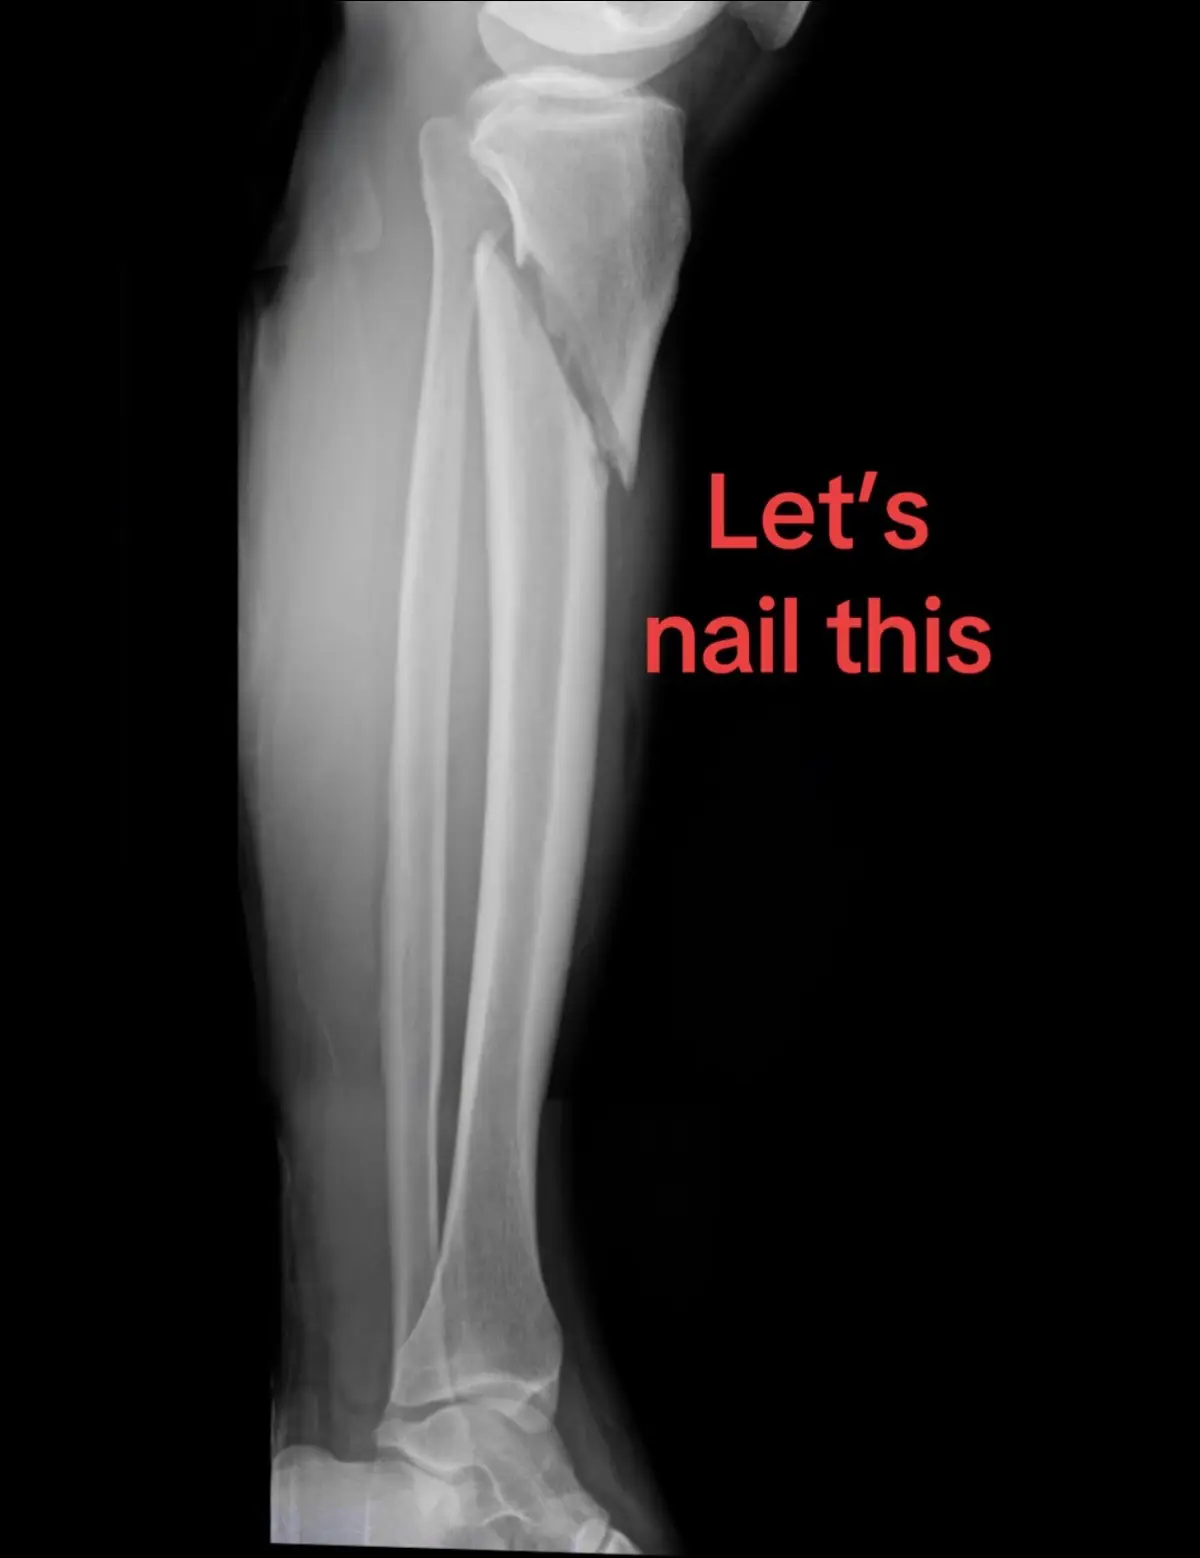

Why a nail? Because it’s much more stable than a plate, minimally invasive, and allows for immediate weightbearing. These like to go into valgus and procurvatum. To avoid that, some technical tips are: ⭐️Semi extended position ⭐️Suprapatellar nailing ⭐️Reduction clamps to reduce the fracture ⭐️A more lateral start point ⭐️A more posterior start point (and aim anterior, not posterior) ⭐️Blocking screws (lateral and posterior in proximal segment) ⭐️Uni cortical plates Remember to allow immediate weightbearing! Used with patient permission #orthotrauma #orthopaedics #orthopedics #tibia #fracture